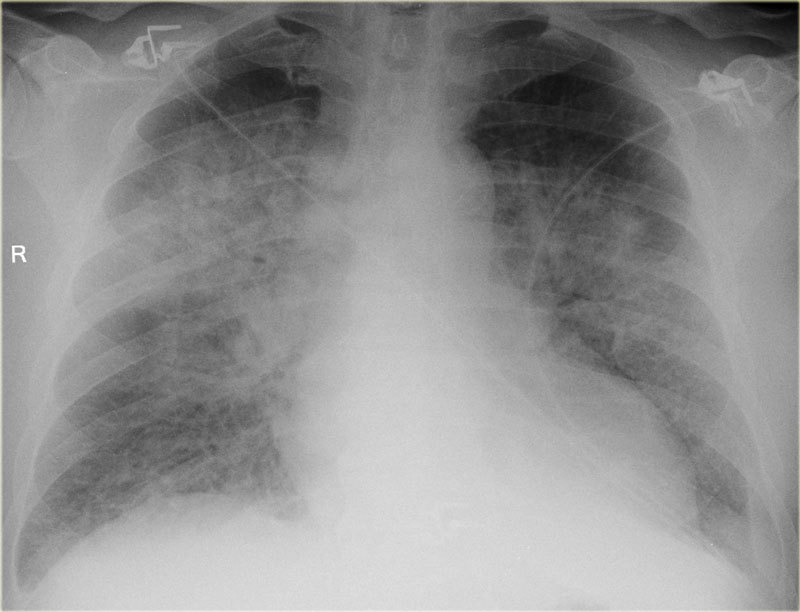

Heart Failure

(- prosthetic valves)

LVA

Pulmonary edema

+- pleural effusions

+- heart failure